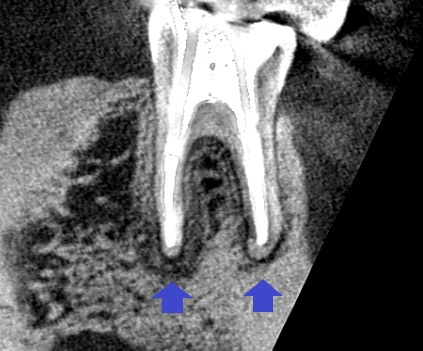

精密根管治療6ヶ月後の経過観察時の矢状断のCT画像です。青い矢印の先にあった膿の影が縮小し歯槽骨が再生してきています。

精密根管治療6ヶ月後の経過観察時の冠状断のCT画像です。青い矢印の先にあった膿の影が縮小し歯槽骨が再生してきています。